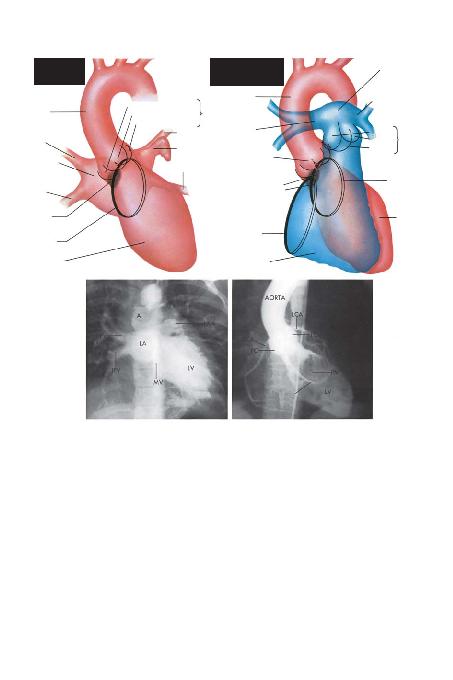

SOL KALBBOfiLUKLARININ

ANTEROPOSTERGÖRÜNTÜSÜ

SOL VENTR

MANNULUSU

MEMBRANÖZ

SEPTUM

SA/ PULMONER

VEN

SA/ SUPERPULMONER

SOL ATR

AORTA

POST. (KORONER OLMAYAN) KUSP

SOL SÜPERPULMONER VEN

SOL AURATR

SOL PULMONER VEN

KATETER

SA/ (KORONER) KUSP

SOL (KORONER) KUSP

SA/ VENTR

TRKAPAK

ANNULUSU

SOL KALBSV: SOL VENTRSUPERSOL ATR

A-P ANGVARKEN: LCA: SOL KORONER ARTER: RCA: SA/ KORONER

ARTER; LC: SOL KUSP; PC: AORT KAPA/ININ POSTERPM: POSTER

MEMBRANÖZ SEPTUMUN

ATR

AORT KAPA/I

AORT

KAPA/I

ARTER

PULMONER TRUNK

SOL PULMONER ARER

SA/ KUSP

ANT. KUSP

SOL KUSP

SOL

VENTR

PULMONER

KAPAK

SOL VE SA/ KALBB(GÖRÜNTÜ NETLATR